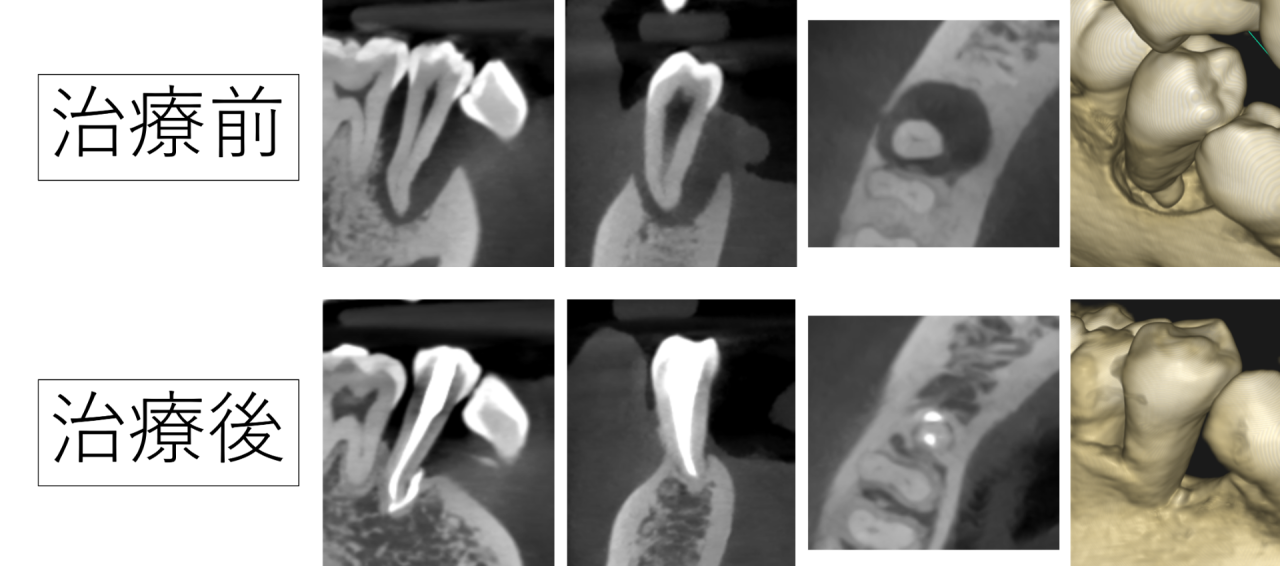

歯茎の炎症や菌の増殖などで「歯が痛む」「腫れが気になる」「食べているとしみる」などの症状を感じたことはないでしょうか。歯周病の治療では、まずは顕微鏡検査で歯を大きく確認しながら、どれくらいの状態なのか、歯茎の中にまで菌が増殖していないかなど、状況を確認してから治療を進めてまいります。

みつおデンタルクリニックでは、マイクロスコープ(顕微鏡)やCTなどのレントゲンによる精密な検査を行っております。そのため、最近では、セカンドオピニオンを求めて来院される患者様が増えてきました。…

患者様の歯の状態や性質などをしっかりと見極め、それぞれの患者様に合う最適な治療方法をご提案しております。例えば、症状が中等度から重度になるにつれて、また歯茎の奥や歯の奥など、見えにくくなる場所の治療になるほど、歯周病の治療には高度な技術や経験、器材が必要になってきます。そのため、治療は歯科衛生士でも担当できますが、高度な技術が必要な治療に関しては院長自らが責任を持って治療を実施します。一人ひとりの歯の健康をお守りできるよう、根本からの改善を目指す高技術な治療を丁寧に実施します。